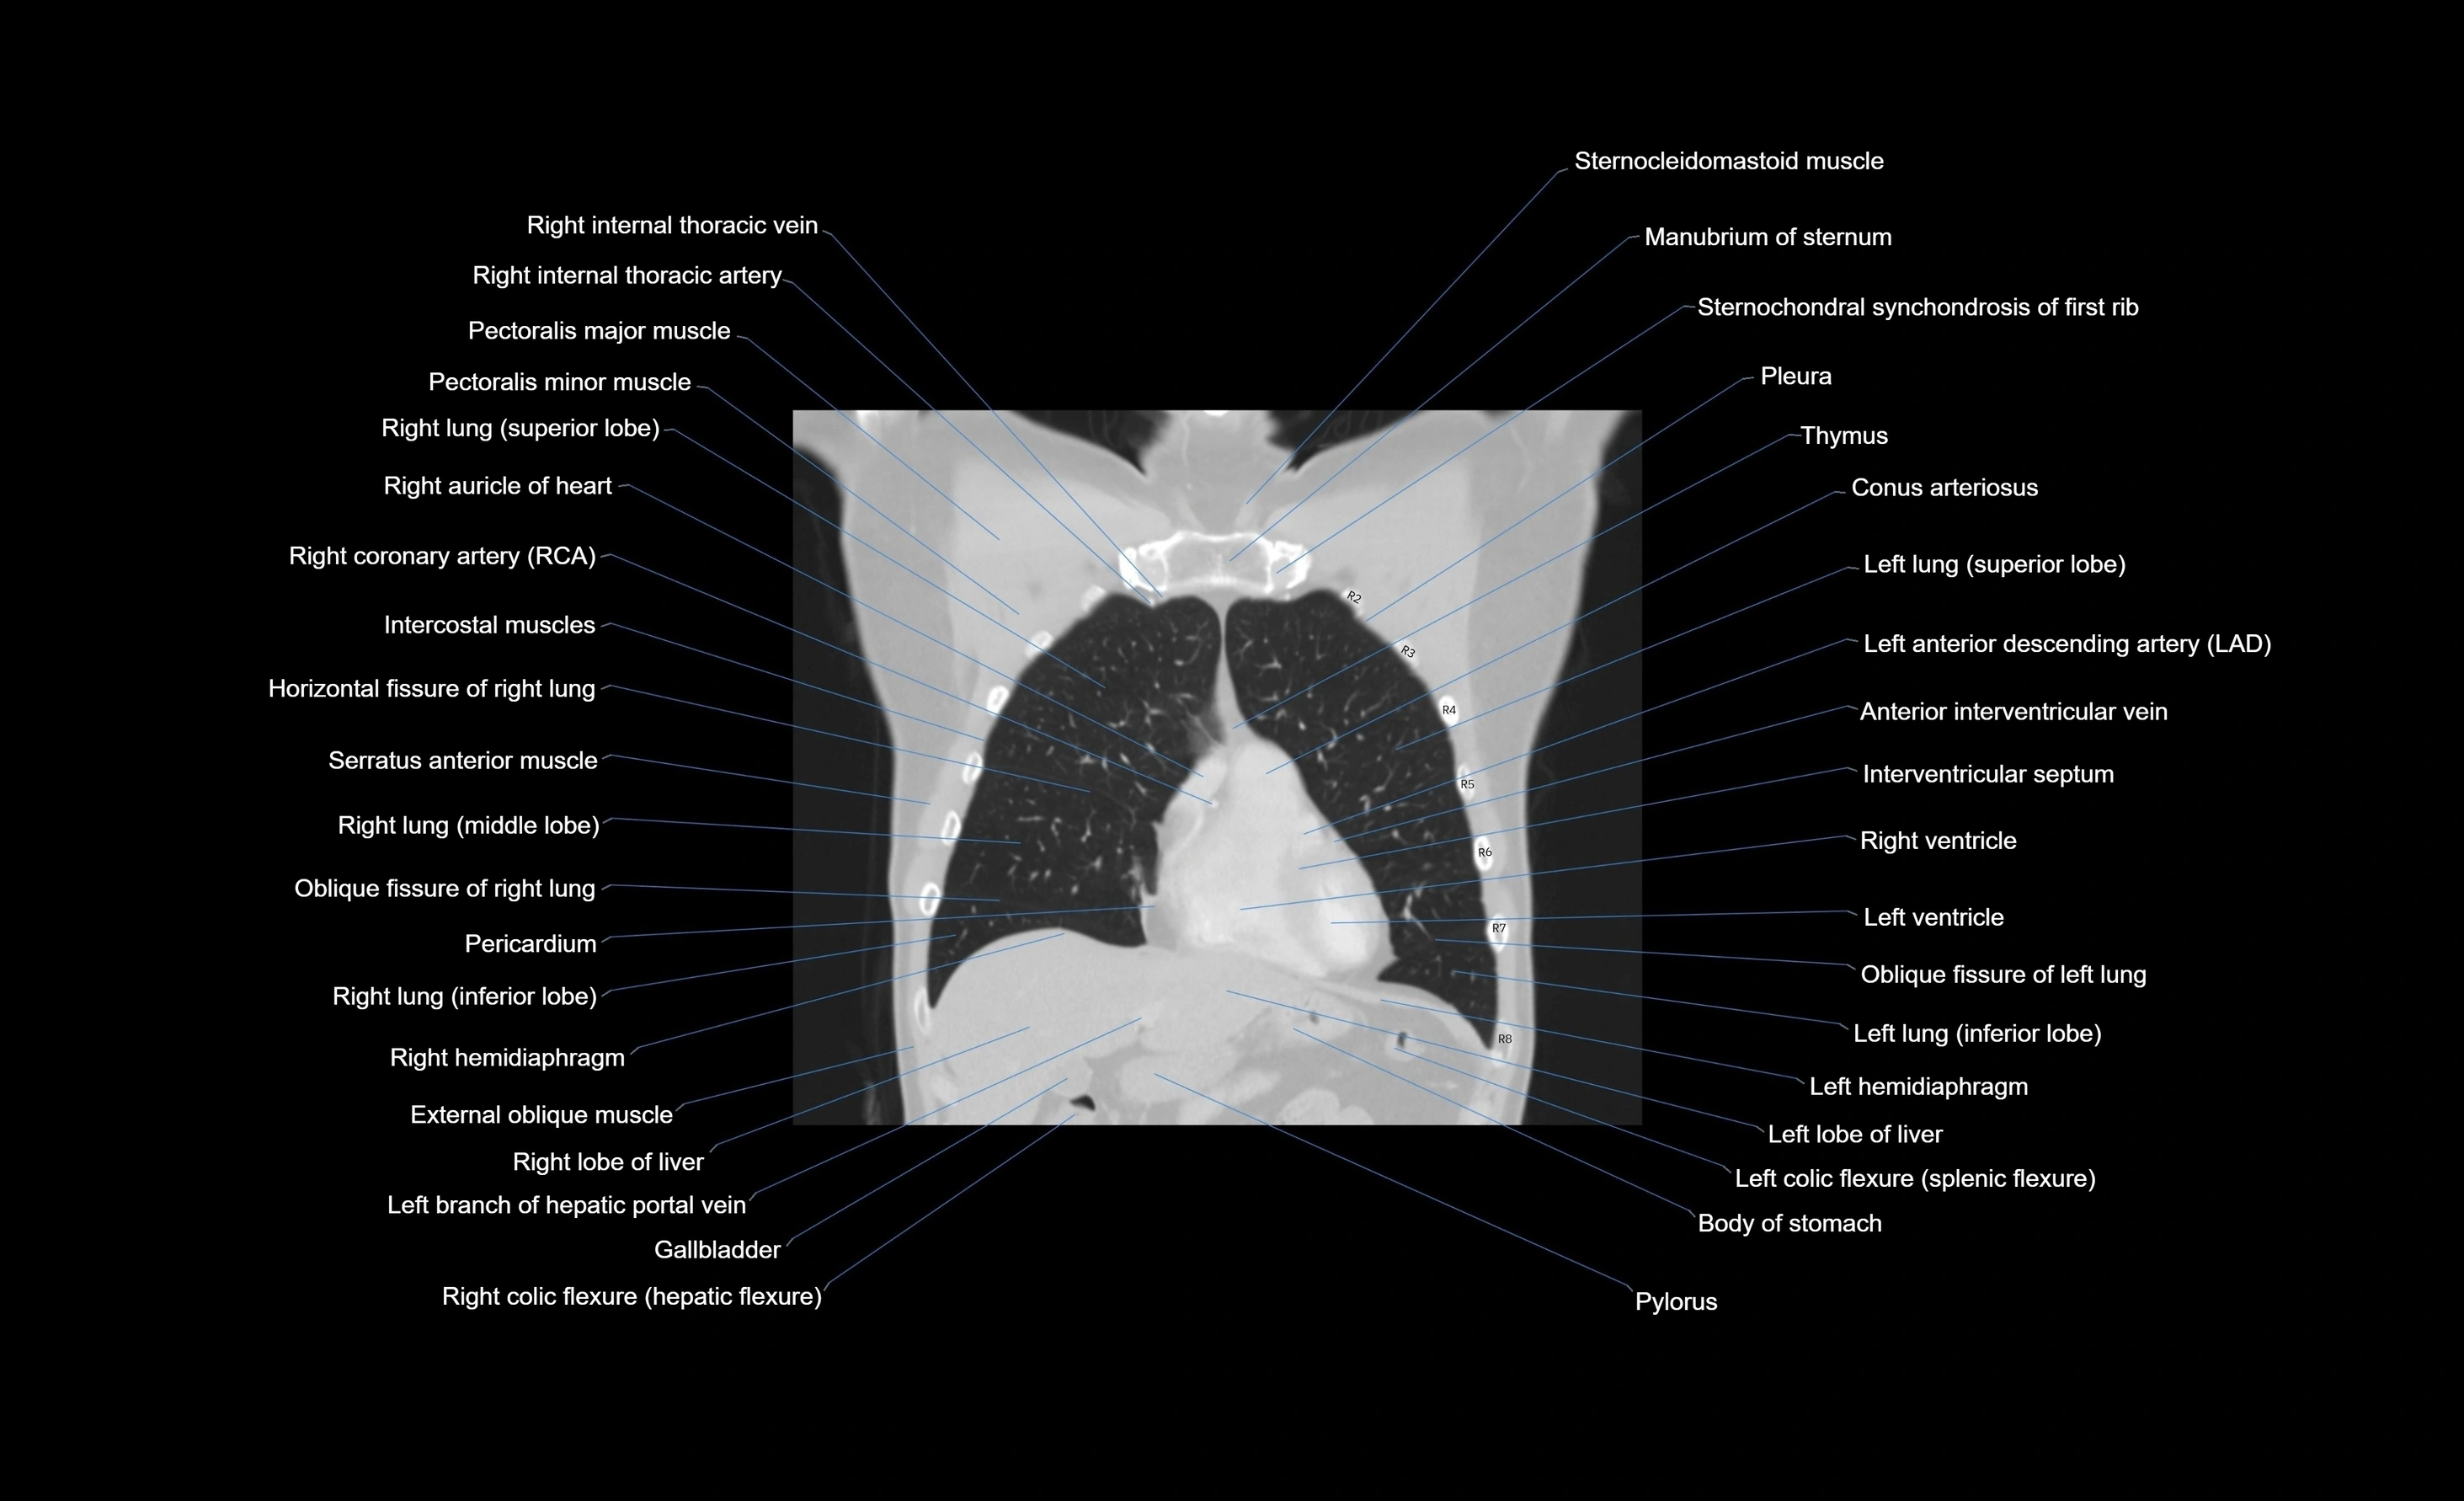

- Conus arteriosus

- Horizontal fissure of right lung

- Intercostal muscles

- Interventricular Septum

- Left anterior descending artery (LAD)

- Left hemidiaphragm

- Left lung (inferior lobe)

- Left ventricle

- Oblique fissure of right lung

- Pectoralis major muscle

- Pectoralis minor muscle

- Pericardium

- Pleura

- Right auricle of heart

- Right coronary artery (RCA)

- Right hemidiaphragm

- Right internal thoracic artery

- Right internal thoracic veins

- Right lobe of liver

- Right lung (middle lobe)

- Right lung (superior lobe)

- Right ventricle

- Sternocleidomastoid muscle